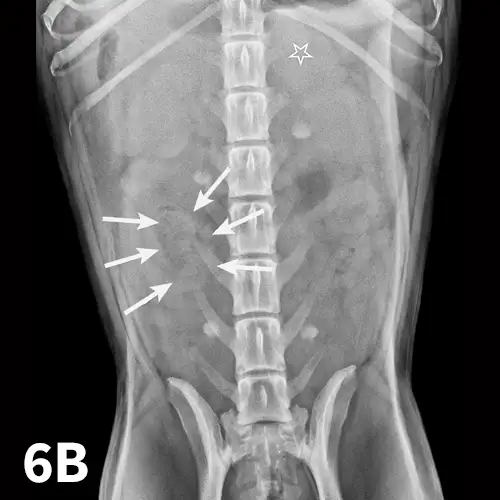

Right lateral (A) and VD (B) abdominal radiographs of a Labrador retriever with an obstructive ileus. A FB (sock) is present within a dilated small intestinal loop in the right caudoventral abdomen (arrows). The dashed lines outline a fluid-filled loop measuring 2.7 cm and a gas-filled loop measuring 2.4 cm, compared to the height of L5 (Asolid line, 1.1 cm);  the resulting ratios of 2.4 and 2.2, respectively, are much greater than the upper limit of 1.6 for normal small intestine to L5 height ratio. Several stacked gas-filled loops of small intestine are present in the left midabdomen (B).